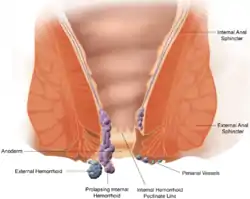

Hæmorider (kan også staves haemorrhoide eller hæmorroide) er vaskulære strukturer i analkanalen, der hjælper til at kontrollere afføringen.[1][2] I daglig tale refererer hæmoride dog til den patologiske tilstand, hvor hæmoriden er hævet eller irriteret. I sin normale (fysiologiske) tilstand virker hæmoriden som en pude af arterielle-venøse kanaler og væv, der hjælper afføringen til at passere. Symptomerne for den patologiske hæmoride afhænger af typen. Interne hæmorider er sædvanligvis smertefrie, men giver ofte blødning fra endetarmen, mens eksterne hæmorider (hæmorider der er tiltaget i omfang, så de ender med at hænge ud af endetarmsåbningen) ofte giver smerter omkring anus. Det anslås at omkring 50% af befolkningen før eller siden får hæmorider.[3]

Skematisk fremstilling af hæmoriders anatomi. | |

Der er to typer af hæmorider – eksterne og interne – der adskilles ved deres placering i forhold til endetarmsåbningen.[5]

Eksterne hæmorider

Eksterne hæmorider er placeret uden for eller i umiddelbar nærhed af endetarmsåbningen og kan således godt være placeret så de ikke umiddelbart er synlige. Mere specifikt er de åreknuder på de vener der drænerer blodet fra de nedre, rektale arterier, der afgrener fra arteria pudenda interna. De er undertiden smertefulde, ligesom der ofte også ses hævelse og irritation. Kløe, der ofte anses for at være et symptom på eksterne hæmorider, skyldes almindeligvis hudirritation i stedet; hævelsen af hæmoriden er årsag til en næsten umærkelig væskeafgift der fører til hudirritation. Eksterne hæmorider fører ofte til trombose; hvis venen sprænges og/eller en blodprop dannes dannes bliver hæmoriden til en tromboseret hæmoride.[6]

Interne hæmorider

Interne hæmorider er de hæmorider der findes i tarmen, væk fra endetarmsåbningen. Mere specifikt er de åreknuder på de vener der drænerer blodet fra de øvre, rektale arterier. Eftersom dette område ikke har smertereceptorer er interne hæmorider sjældent smertefulde. De fleste mennesker er ikke klar over at de har dem. Interne hæmorider kan dog begynde at bløde hvis de irriteres. Hvis ikke de behandles kan interne hæmorider føre til to alvorligere former for hæmorider, henholdsvis prolapserende og afklemte hæmorider. Prolapserende hæmorider er interne hæmorider der er tiltaget i omfang så de skubbes uden for endetarmsåbningen. Hvis lukkemusklen begynder at krampe og således fanger en prolapserende hæmoride uden for endetarmsåbningen afklemmes dens blodforsyning og hæmoriden bliver til en afklemt hæmoride.